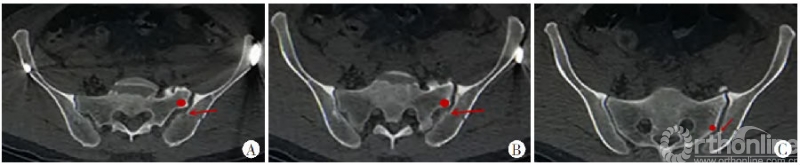

新月形骨折病例解剖学分型III型:

图10 A.横断面:内板骨折线自骶骨侧嵴(红色圆点)的后方进入骶髂关节,髂骨骨折通常为撕脱骨折的表现,骨折块小,一般不波及髂骨外板,但骶髂关节大部分受累,骶髂关节间隙增大;B.冠状位:内板骨折线自骶骨侧嵴(红色圆点)的后方进入骶髂关节,髂骨骨折部分为撕脱骨折的表现;C.固定方式采用骶髂螺钉

骶骨后方外侧嵴距离髂骨后缘有一定距离,主要为韧带附着点,在侧方挤压暴力作用下,骶髂后方产生张力,所以其骨折主要表现为髂骨的撕脱骨折,即为病理解剖学分型Ⅲ型。

病理解剖学分型III型较小的新月形骨折块,常为撕脱骨折,其骨损伤相对较小,但波及更大范围的骶髂关节,甚至并发严重的骶骨压缩骨折,可经皮复位,骶髂螺钉置入[4、9、17]。